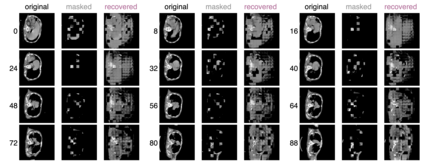

Recently, masked image modeling (MIM) has gained considerable attention due to its capacity to learn from vast amounts of unlabeled data and has been demonstrated to be effective on a wide variety of vision tasks involving natural images. Meanwhile, the potential of self-supervised learning in modeling 3D medical images is anticipated to be immense due to the high quantities of unlabeled images, and the expense and difficulty of quality labels. However, MIM's applicability to medical images remains uncertain. In this paper, we demonstrate that masked image modeling approaches can also advance 3D medical images analysis in addition to natural images. We study how masked image modeling strategies leverage performance from the viewpoints of 3D medical image segmentation as a representative downstream task: i) when compared to naive contrastive learning, masked image modeling approaches accelerate the convergence of supervised training even faster (1.40$\times$) and ultimately produce a higher dice score; ii) predicting raw voxel values with a high masking ratio and a relatively smaller patch size is non-trivial self-supervised pretext-task for medical images modeling; iii) a lightweight decoder or projection head design for reconstruction is powerful for masked image modeling on 3D medical images which speeds up training and reduce cost; iv) finally, we also investigate the effectiveness of MIM methods under different practical scenarios where different image resolutions and labeled data ratios are applied.